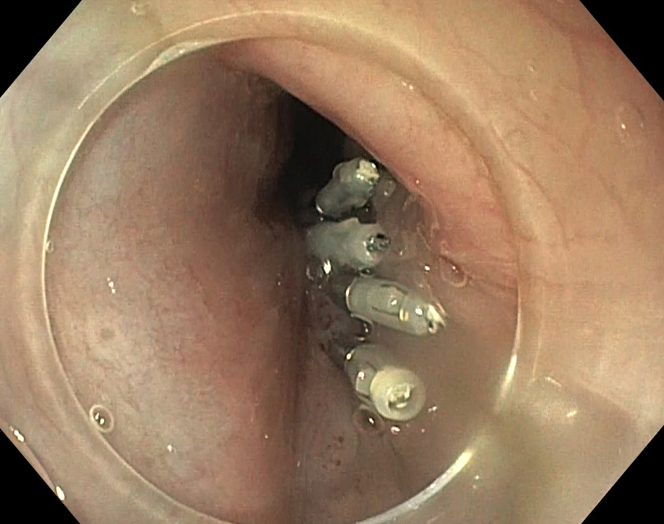

Figure 6.

Closure of mucosal incision with multiple endoclips.